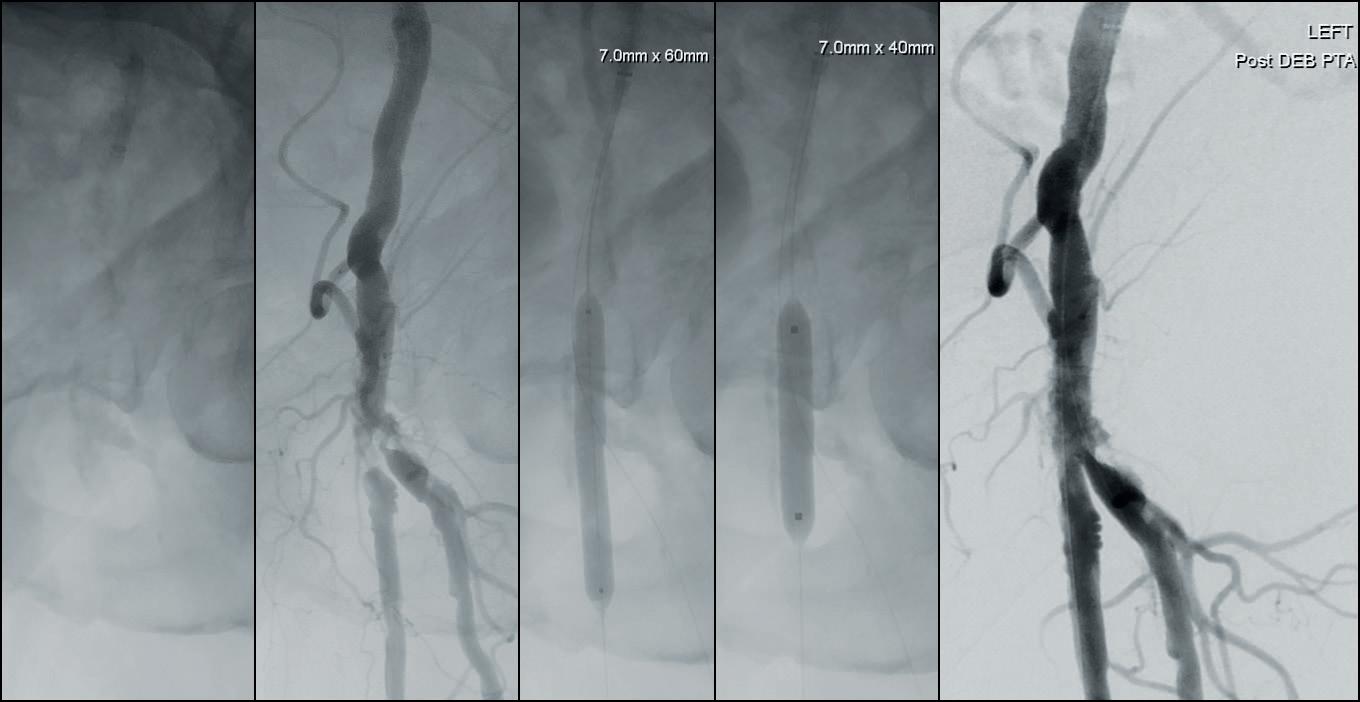

3. Treatment of a calcified stenosis of the left common femoral artery bifurcation with a 7.0x60mm IVL catheter, followed by a 7.0x40mm DCB

Since IVL does not address neointimal hyperplasia, it was hypothesized that the addition of a drug-coated balloon (DCB) plus IVL may have the potential to further improve long-term results in this challenging patient population. DISRUPT PAD III is a randomized study designed to assess that strategy. This trial has completed enrollment and results are eagerly awaited. Today, Shockwave IVL has been used to treat calcified peripheral arterial occlusive disease in a wide range of anatomic locations. A large observational registry has provided independent Core Laboratory adjudication of acute procedural outcomes and confirmed excellent safety and efficacy. Interestingly, IVL is usually followed by an adjunctive therapy but this differs depending on the anatomic location. In the femoral artery, IVL is most commonly followed by DCB angioplasty; in the iliac artery, IVL is usually followed by stenting. The aortoiliac segment has been an area of recent interest where IVL has been used to successfully dilate calcified iliac arteries to facilitate EVAR or in aortoiliac occlusive disease. The common femoral artery has also been a new and successful application for IVL (Figure 3).

Subsequent diagnostic angiography confirmed the high grade left CFA stenosis (Figure 1) and the long SFA occlusion with diminished contrast flow below the knee. The deep femoral artery showed no significant stenosis within the first centimetres. For

In this case example, a 79-year-old man with severe claudication of the left leg was admitted to our angiology department. Cardiac risk factors included poorly controlled diabetes, renal insufficiency (GFR 27ml/min), severe obesity (body mass index [BMI] 38) and hyperlipoproteinaemia. On duplex ultrasound, a severe calcified short 90% CFA stenosis and a long 30cm occlusion of the superficial femoral artery (SFA) from the origin to popliteal artery (PA) segment one was diagnosed. The posterior tibial artery

DCB PTA catheter, BD Bard) which was inflated for three minutes at 8atm. Subsequent angiography showed a very good lumen gain without significant restenosis within the target lesion (Figures 3 and 4). We finalized the intervention with full recanalisation of the SFA using three more DCBs and one bailout stent implantation using the new triaxial, 4F Pulsar-18 T3 nitinol self-expanding stent system (6x150mm; Biotronik). After implantation of the Pulsar-18 T3 stent and a 6mm balloon post dilatation, a brisk flow was seen within the whole length of the target vessel and a straight flow into the foot via the patent posterior tibial artery. Follow-up examination of the patient the next day showed an ABI of 0.9 on the left side.

recanalization, a crossover approach from the right groin was performed using an 8F crossover Destination reinforced introducer sheath (Terumo). Using an 0.014” Glidewire Advantage guidewire we were easily able to pass the high-grade CFA stenosis with the guidewire.

A 7x60mm IVL catheter was delivered across the lesion and the integrated balloon was expanded to 4atm to facilitate efficient energy transfer. After four calcium modification cycles, we used the integrated balloon to dilate the lesion at 6atm pressure in order to maximize luminal gain. The IVL catheter was then exchanged to an 8x40mm drug-coated balloon (DCB; Lutonix 035